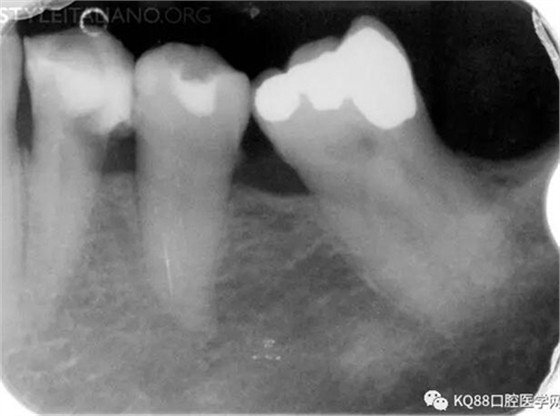

Img. 4 - Case 2: This necrotic first mandibular molar was treated in one visit, and the patient complained of post-operative pain. Analgesics and antibiotics were prescribed, and occlusion relieved. Symptoms disappeared after two days, and a radiographic follow-up after two years showed healing of the periradicular lesion.